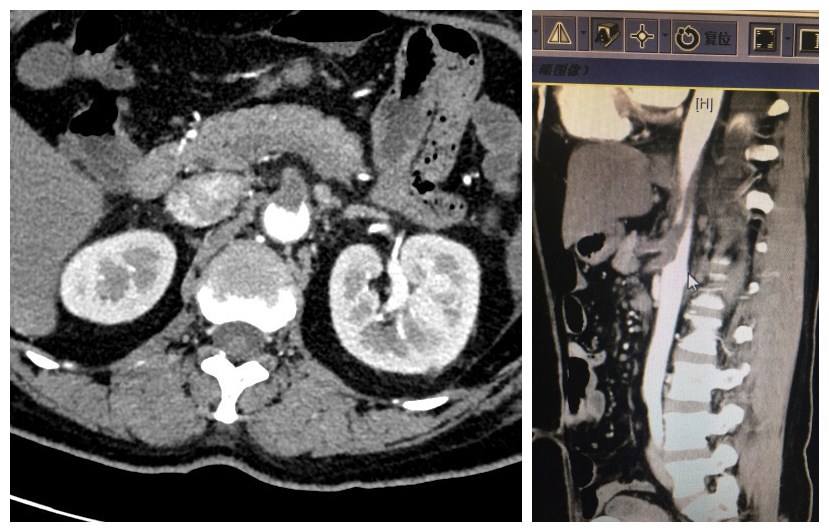

病例一:患者男,70岁,1个月来腹胀,间断全腹疼痛,10天来腹痛加重。于外院诊为肠梗阻,经禁食水、补液治疗后无缓解,来我院急诊。既往冠心病、房颤病史20年。经检查后发现门静脉及肠系膜静脉血栓形成,考虑存在肠坏死,遂行急诊手术。术中见2.2m小肠缺血,部分坏死,相应肠系膜静脉广泛血栓。予肠切除并由血管外科行肠系膜上静脉切开取栓治疗,将远近断端肠管分别提出腹壁并造瘘。术后患者经抗凝、补液抗炎治疗恢复良好,逐渐由胃肠外营养过渡到经回肠造瘘口灌注营养液。

病例二:女,45,近一周来腹痛,加重2天。于外院检查后考虑肠系膜上动脉血栓形成,转来我院进一步治疗。急诊腹部增强CT显示:腹腔干动脉、肠系膜上动脉栓塞,腹主动脉内长段漂浮血栓,急诊手术探查,肠管未见坏死,行肠系膜上动脉切开取栓+主动脉覆膜支架置入隔绝腹主动脉内血栓。术后筛查患者为遗传性抗凝血酶III缺乏症,运用利伐沙班抗凝,并逐渐由胃肠外营养恢复到肠内营养,病情稳定后出院,院外继续抗凝治疗。